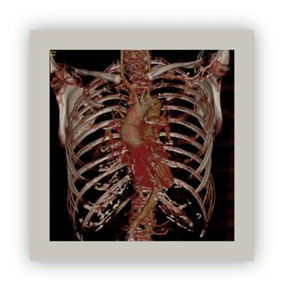

Volume rendering (VR)

This technique uses all the volume data represents multiple structures and their relationships. Volume Rendering provides a three-dimensional view of the structures posterior to the section, facilitating the understanding of the section (Figure 8).28

Figure 8 Thorax CT 3d volume rendering.